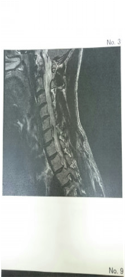

「首の調子がずっと悪い。最近は右腕のしびれも強い。 頚椎ヘルニアが疑われるので、その旨説明し、話し合いの上、当面は症状改善の治療をしてラン継続。 |

![]() |

| 院長より | |

| 後日、検査(MRI)で頚椎のヘルニア確定しました。 当院で保存的な治療を継続中です。ランニングも続けておられます。 |